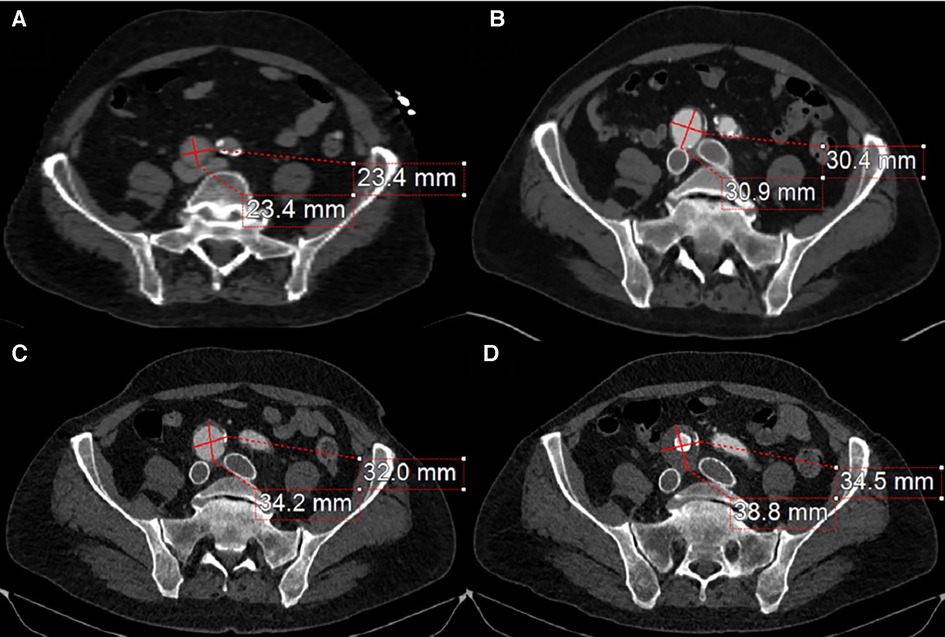

Follow-up imaging 6 months later demonstrated an increase in the size of the right CIA aneurysm (Figures 3B,C). Therefore, the patient was taken for a staged intervention of the aneurysm with the placement of covered iliac stents using a 13.5 mm Fluency self-expanding (Bard Peripheral Vascular, Tempe, AZ, USA) and 10 mm iCast stents (Atrium, Hudson, NH, USA) in overlapping fashion from the ostium of the right CIA to the bifurcation of the internal–external iliac arteries. These stents were chosen due to sizing availability at the time over the traditional EVAR limb. The Fluency stent was initially used as it would result in adequate coverage without an obvious endothelial leak. Once the covered stent was placed in the proximal CIA, we proceeded with placing a 1:1-sized iCAST stent to ensure appropriate coverage of the aneurysmal segment. Follow-up CTA demonstrated a regression and thrombosis of the aneurysm and patent, well-aligned venous stents, Figure 3D. The near resorption of the native aneurysm sac can be discerned from Figures 4A,B. Because of the placement of the stents and resumption of anticoagulation, the patient has had no further reoccurrences of DVTs or other related symptoms.

Figure 3. (A) The compressive effects of the right CIA on the bilateral iliac veins. (B) 4-month post-bilateral iliac venous stenting showed venous stent patency but also demonstrated an interval increase in right CIA aneurysm size. (C) 12-month follow-up from initial venous intervention demonstrates a progression in aneurysmal size. (D) 1-month post-stenting to the right common iliac artery stent graft traversing the aneurysm with a noticeable thrombus of the aneurysm sac and patent iliac artery stent.